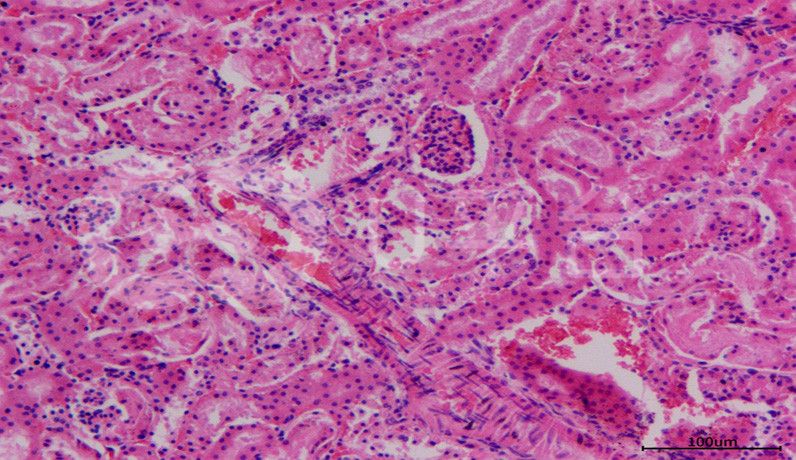

HE染色實操注意事項由普拉特澤生物旗下科研培訓品牌《春風學院》總結分享,文尾附有HE染色視頻教程供大家學習。蘇木精—伊紅染色法簡稱HE染色法,是最常用的普通染色方法,普拉特澤生物病理實驗平臺在大量的實戰中積累了豐富的經驗,快來聽聽分享吧!